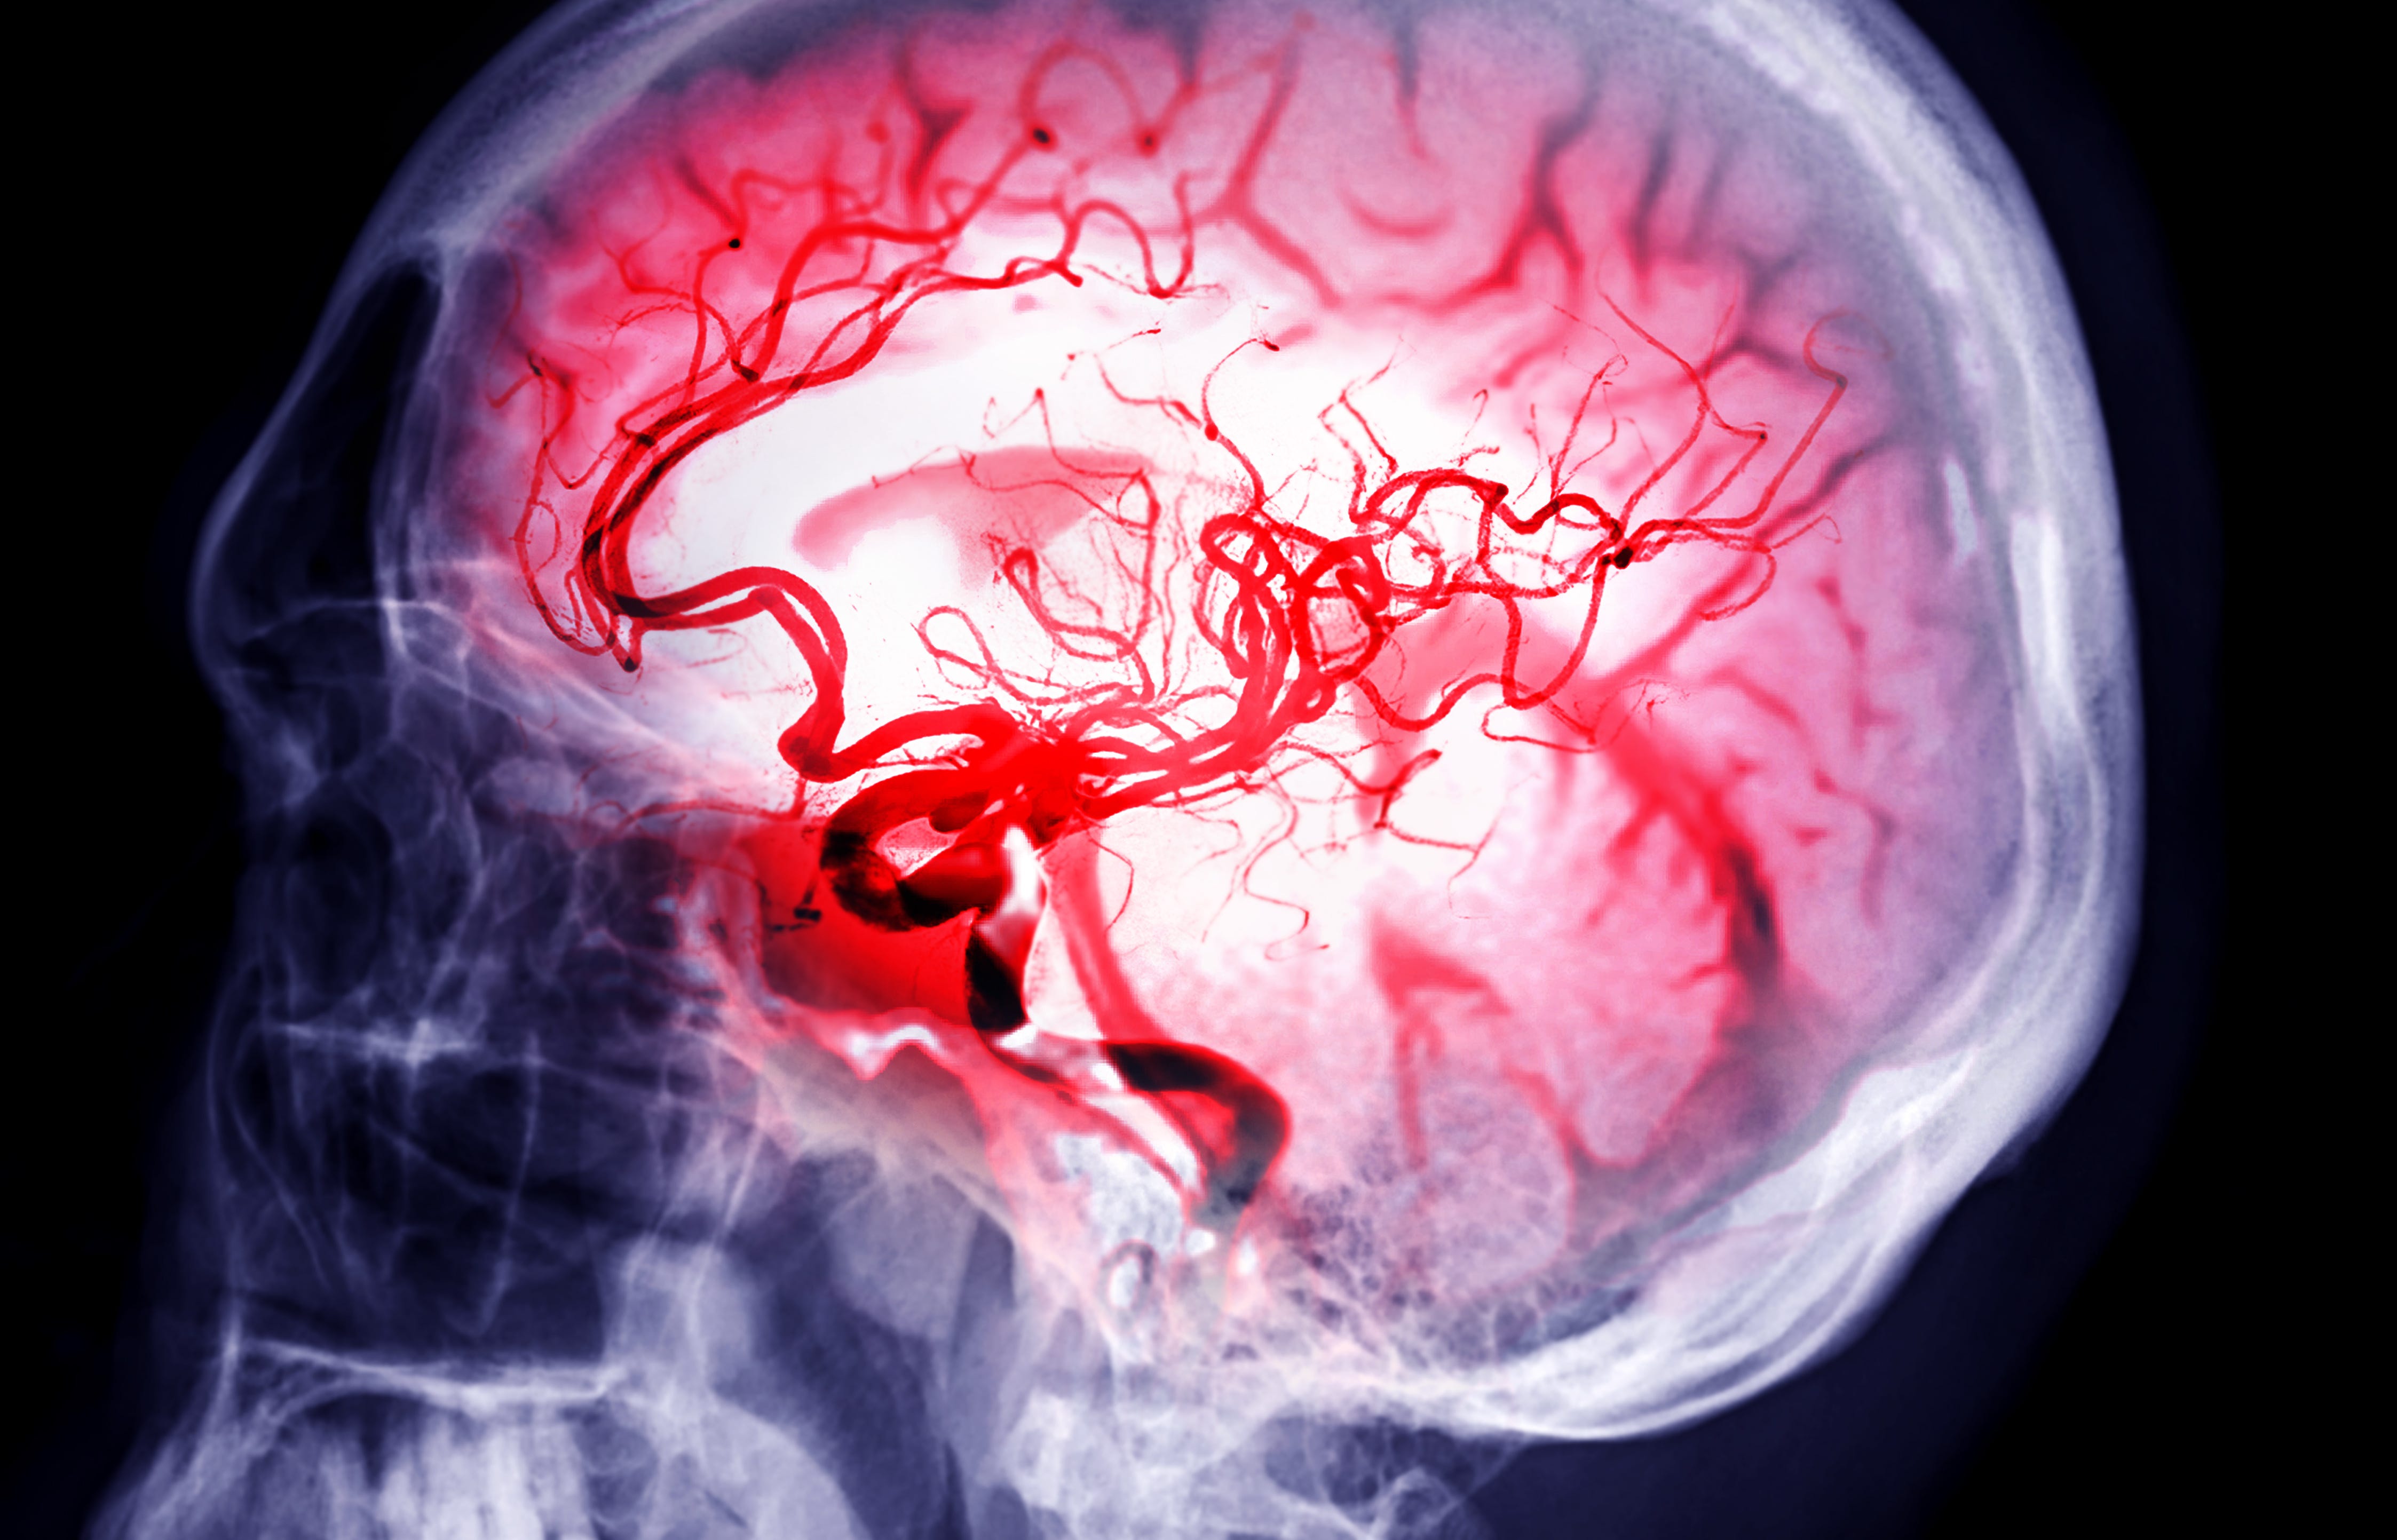

Patients who present with ischemic stroke more than 4.5 hours after symptom onset generally do not receive intravenous thrombolytics (tPA or TNK). That’s because outside that accepted window, the risk of intracranial hemorrhage was believed to outweigh the benefits of thrombolytics in restoring blood flow to at-risk brain tissue.

At least 8 randomized trials have been published testing IV thrombolytics given more than 4.5 hours after stroke symptom onset. None of the enrolled patients underwent mechanical thrombectomy (that was tested in other trials), and all underwent specialized brain imaging studies to ensure they had salvageable brain tissue.

These trials all used advanced imaging techniques to identify patients who might have salvageable brain tissue: either perfusion imaging (CT/MRI) or diffusion-weighted imaging (MRI).

These imaging modalities are not rapidly available during “code strokes” in most community centers, which rely solely on non-contrast CT to make treatment decisions for ischemic stroke.